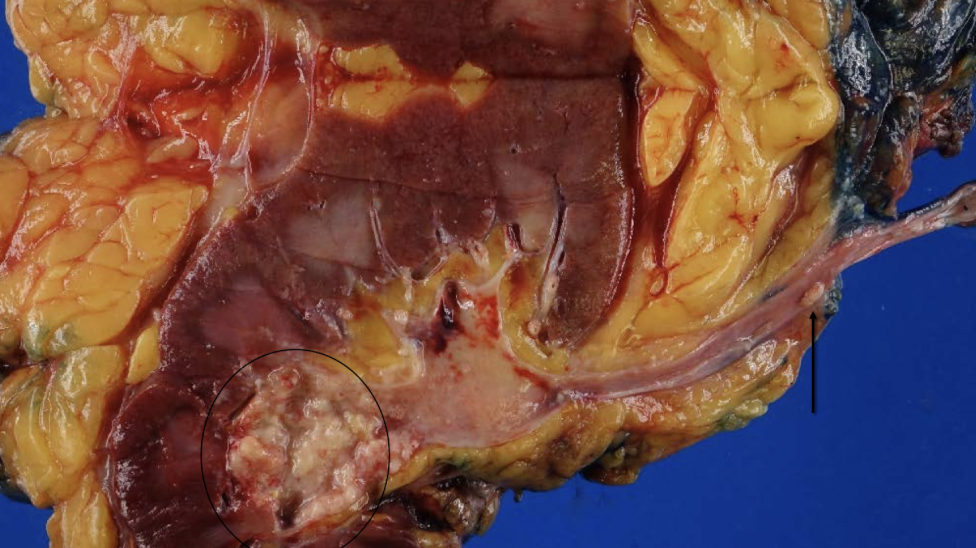

xanthogranulomatous pyelonephritis

proteus (>50%), E coli, pseudomonas, klebsiella

urine cultures negative!!

palpable mass that can mimic tumor

UT obstruction, staghorn, DM

xanthogranulomatous pyelonephritis

pus, scarring, stones

xanthogranulomatous pyelonephritis

sheets of foamy, lipid-laden macrophages